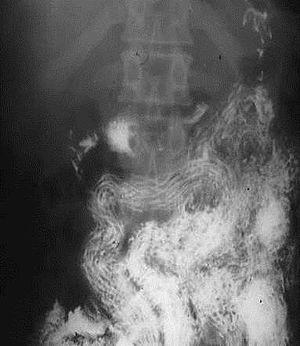

Ascaris infection in the x-ray image- ascaris arranged tidily along the long axis of the small bowel (South Africa) (16424840021).jpg

Ascaris worms (one type of helminth) in the small bowel of an infected person (X-ray image with barium as contrast medium)